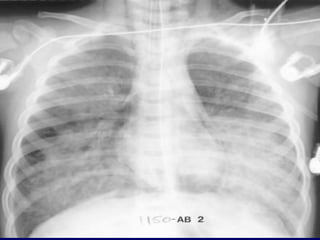

EMPHYSEMA

Permanent, abnormal enlargement of air

spaces distal to the terminal bronchiole

and accompanied by the destruction of

the walls of the involved air spaces.

Emphysema typically presents as

areas of low attenuation without

visible walls as a result of

parenchymal destruction.